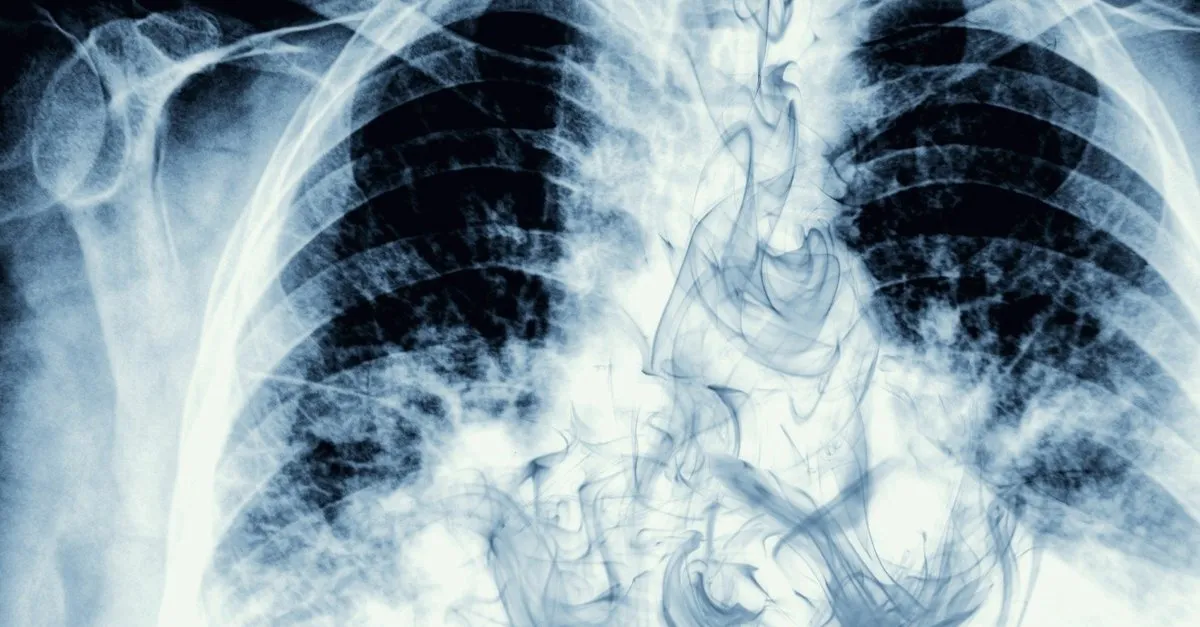

Akciğer kanseri teşhisinde röntgen ve diğer tetkiklerin yapılması oldukça önemlidir.

Birçok insan akciğer kanseri röntgende çıkar mı sorusunun cevabını merak etmiştir. Tüm dünyada ve ülkemizde en sık görülen kanserlerin başında gelen akciğer kanseri günümüzde giderek yaygınlaşıyor. Kanserle dans derneği tarafından akciğer kanseri farkındalık ayı kapsamında kanserle dans basın buluşmaları akciğer kanserinde erken tanı ve yeni geliştirilen tedaviler konulu etkinlik düzenlendi. Türkiye de çok yaygın olan demir eksikliği anemisinden mevsimsel şartlara günlük hayatın yoğun koşuşturmacasından psikolojik sıkıntılara dek birçok nedenden kaynaklanabilen halsizlik günlük.